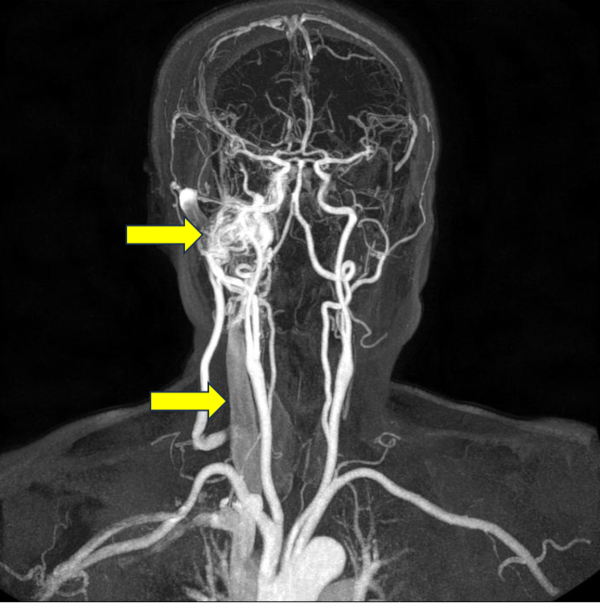

박동성 이명은 다양한 혈관성 질환이 원인일 수 있다. 그 중 하나는 동정맥루이다. 동정맥루는 동맥과 정맥이 비정상적으로 직접 연결된 상태로, 정맥으로 혈액이 비정상적으로 빠르게 이동하면서 전반적인 혈관 저항이 감소하고, 이것을 보상하기 위해 심장이 더 강하고 빠르게 뛰면서 귀에서 심장 박동 소리가 들리게 된다. 동정맥루를 방치할 경우 뇌신경병증, 뇌출혈, 뇌경색 등 다양한 합병증으로 이어질 수 있어 조기 진단과 치료가 중요하다.

경동맥 협착 역시 주요 혈관성 원인 중 하나이다. 경동맥의 좁아진 부위에서 혈액이 빠르게 흐르며 “두근두근”거리는 소리나 “와그락”거리는 소리를 일으키는 것이다. 협착이 심해질 경우 뇌졸중 위험이 급격히 증가하며, 보통 경동맥 협착을 지닌 환자는 심장병이나 말초혈관질환이 동반되는 경우가 많아 심근경색의 위험도 증가한다.

박동성 이명은 이비인후과적 문진 및 신체검사뿐만 아니라 다양한 혈관성 질환과도 연관이 되어있기에 혈관 조영 검사나 CT, MRI등의 영상 검사 진단이 필요할 가능성이 높다.